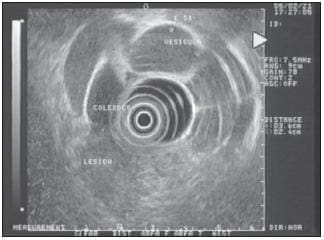

La ecoendoscopia biliopancreática (figura 13) ha demostrado ser superior, en cuanto a precisión y rentabilidad diagnóstica, a la ecografía convencional y a la TC y, al menos, igual a la colangiopancreatografía retrógrada endoscópica (25). Recientemente, la aparición de la TC helicoidal y de la colangiografía por resonancia magnética han abierto de nuevo la polémica sobre la mayor o menor eficacia de cada una de estas técnicas en el campo de la enfermedad biliopancreática. Por otra parte, las posibilidades ya conocidas de la ecoendoscopia se han visto aumentadas por poderse realizar ecoendoscopiapunción aspiración con aguja fina, así como por la disponibilidad de minisondas que, introducidas por vía transpapilar o transhepática, permiten una exploración de la luz de la vía biliar (26) En el momento actual, la mayor utilidad de una u otra de estas técnicas sigue dependiendo de las condiciones locales, como la experiencia del ecoendoscopista, la disponibilidad de la técnica, etc.

FIGURA 13. La ecoendoscopia es útil para detectar microlitiasis, tanto en el colédoco como en la vesícula. En este caso, se observa en la parte superior de la vesícula un microcálculo.

En un estudio comparativo entre la ecoendoscopia y la colangiografía por resonancia magnética realizado en un número limitado de pacientes con sospecha de coledocolitiasis, el ultrasonido endoscópico tuvo una especificidad superior a la colangiografía por resonancia magnética (27). De hecho, la ecoendoscopia ha demostrado ser superior tanto a la resonancia magnética (RM) como a la colangiopancreatografía retrógrada endoscópica (28,29) en el diagnóstico de la microlitiasis (figura 14), por lo cual se considera que es la técnica con mayor precisión en el diagnóstico de coledocolitiasis. Además, no hay que olvidar que la ecoendoscopia evita la colangiopancreatografía retrógrada endoscópica no indicada en 87% de los casos, como se demostró en un estudio con seguimiento clínico durante un año (30) Esto es fundamental si se tienen en cuenta las complicaciones de la colangiopancreatografía retrógrada endoscópica que, incluso, han llevado a la muerte a muchos pacientes.

FIGURA 14. Imagen hiperecoica en el centro del colédoco que produce sombra acústica posterior, indicativa de coledocolitiasis.